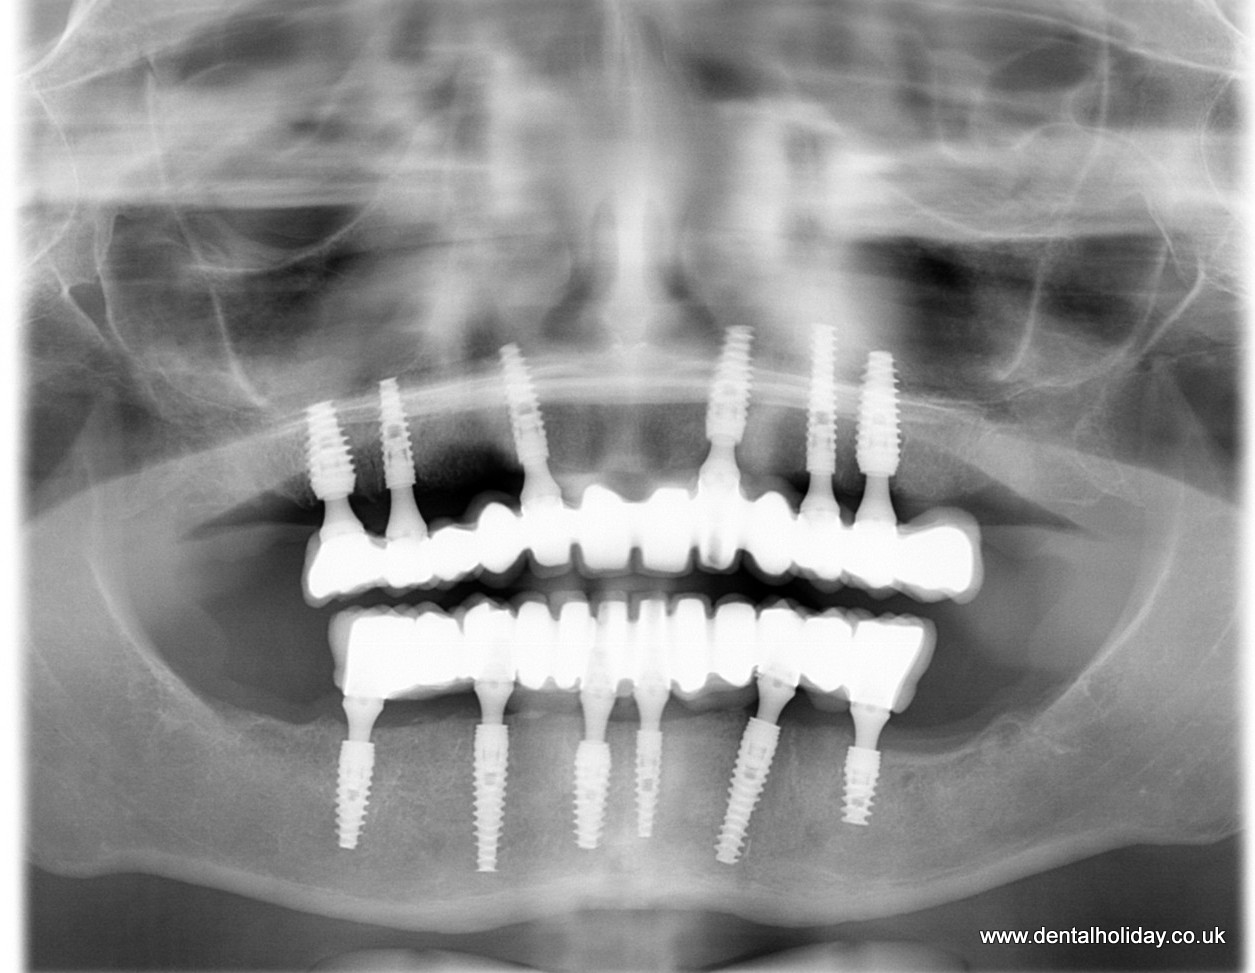

This case study details exactly how Janice’s dental treatment abroad progressed and here are the x-rays before and after for you to see before you read how the treatment progressed.

Janice wanted to have full upper and lower jaw replacement with dental implants, so Dr.Marek due to the weak bone structure that was present, planned to place 6 dental implants for her upper jaw and 6 dental implants for her lower jaw together with a 12 unit non-removable ceramic bridge fitted over upper and lower dental implants. The overall healing after the implant placement was advised for 3 months.

On the next day after the dental consultation and health check she began her dental treatment at the clinic. While she was asleep, all her upper and lower dental implants were placed during general anaesthetic and the temporary bridge was fitted.

Another visit was scheduled for 3 months later for impressions to be made of her teeth. At this stage shape and shade of her teeth were discussed. For the permanent bridge work to be completed our on-site dental technicians need approximately 3 weeks. Therefore on her 3rd visit a few weeks later her ceramic teeth were fitted, and the case complete.